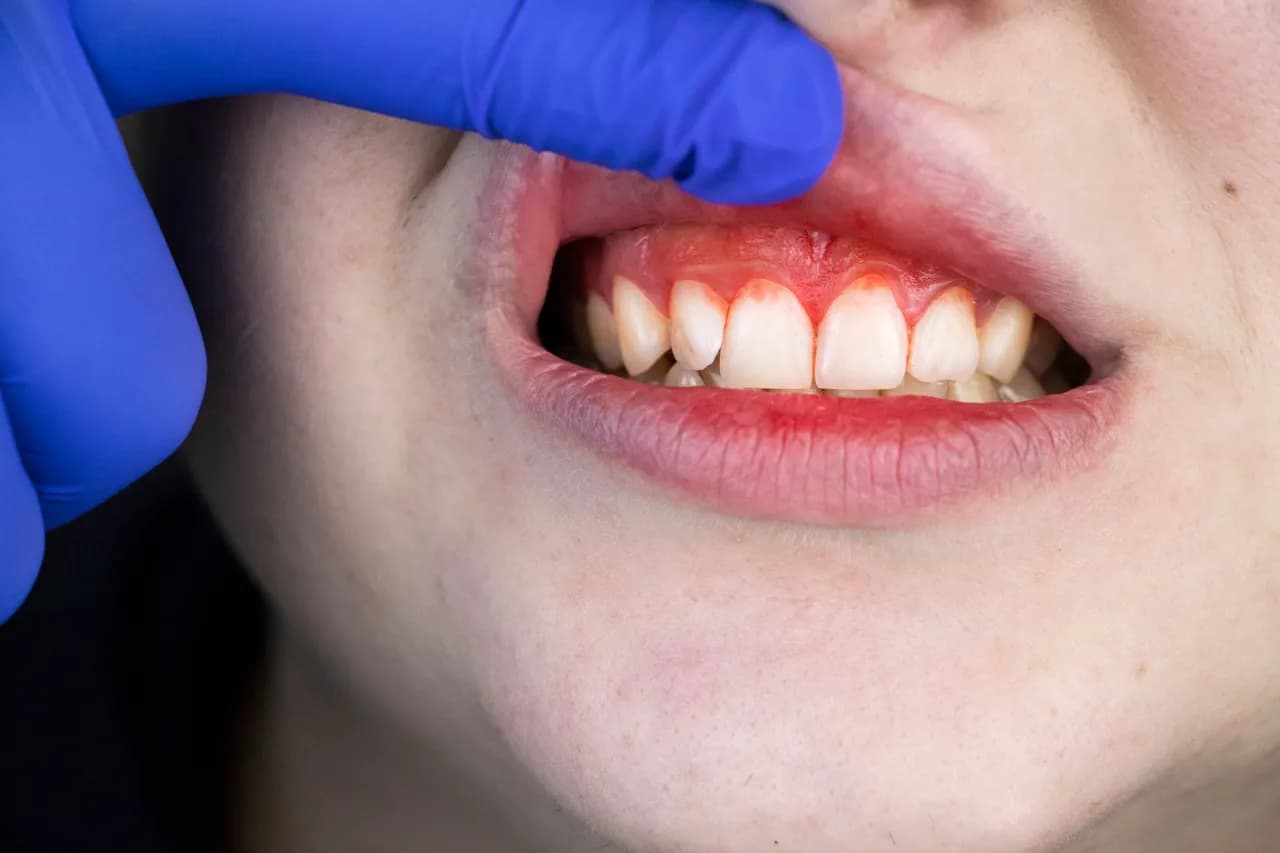

Rak dziąseł to nowotwór, który może przybierać różne formy, a jego wizualne objawy są kluczowe dla wczesnej diagnozy. Najczęściej pojawia się jako średniej wielkości guzek na dziąśle, który pacjenci opisują jako twardą, zgrubiałą „kulkę”. Zmiany te mogą być zlokalizowane w okolicy zębów trzonowych i mogą prowadzić do powstawania owrzodzeń, które nie goją się przez dłuższy czas. W miarę rozwoju choroby, objawy mogą się nasilać, co może prowadzić do poważnych komplikacji zdrowotnych.

Rozpoznawanie tych wizualnych zmian jest niezwykle ważne. Wczesne zauważenie guzków czy owrzodzeń może znacząco zwiększyć szanse na skuteczne leczenie. Zmiany te mogą być również objawem zaawansowanej choroby, co może prowadzić do poważniejszych problemów, takich jak przerzuty do węzłów chłonnych. Dlatego każda niezagojąca się zmiana w jamie ustnej, która utrzymuje się dłużej niż dwa tygodnie, powinna być natychmiast oceniona przez specjalistę.

Aby rozpoznać raka dziąseł, należy zwrócić uwagę na konkretne cechy guzków i owrzodzeń. Guzki mogą mieć różne rozmiary – od kilku milimetrów do kilku centymetrów. Ich kolor może się różnić, od białego przez różowy, aż po ciemnoczerwony. Tekstura guzków może być twarda lub miękka, co również jest ważnym czynnikiem w rozpoznawaniu. Owrzodzenia z kolei często mają nierówne brzegi i mogą wydzielać nieprzyjemny zapach, co jest oznaką stanu zapalnego.

W celu lepszego zrozumienia, jak wygląda rak dziąseł, warto zapoznać się z przykładami zdjęć zmian nowotworowych. Takie obrazy mogą ukazywać różnorodne formy zmian, od guzków po owrzodzenia, które są kluczowe dla wczesnej diagnozy. Na przykład, zdjęcia mogą przedstawiać twarde guzki w okolicy zębów trzonowych oraz owrzodzenia, które nie goją się przez dłuższy czas. Obserwacja tych zmian jest istotna, ponieważ mogą one wskazywać na zaawansowany stan choroby.

Interpretacja zdjęć zmian nowotworowych na dziąsłach wymaga uwagi na kluczowe cechy, które mogą wskazywać na obecność raka. Przede wszystkim, należy zwrócić uwagę na kształt zmian; guzki powinny być twarde i zgrubiałe, a owrzodzenia mogą mieć nierówne brzegi. Kolor zmian również ma znaczenie – zmiany mogą być białe, czerwone lub ciemnoczerwone, co może sugerować różne stany patologiczne. Ponadto, ważne jest, aby ocenić, czy zmiany są statyczne czy też się rozwijają, co również wpływa na diagnozę.

W przypadku zdjęć, które wykazują cechy zapalne, takie jak obrzęk lub zaczerwienienie, również powinny być brane pod uwagę. Dokładna analiza tych cech jest kluczowa dla postawienia właściwej diagnozy i podjęcia odpowiednich działań terapeutycznych. Warto, aby pacjenci konsultowali się z lekarzem w celu omówienia wszelkich niepokojących zmian, które zauważą na zdjęciach.